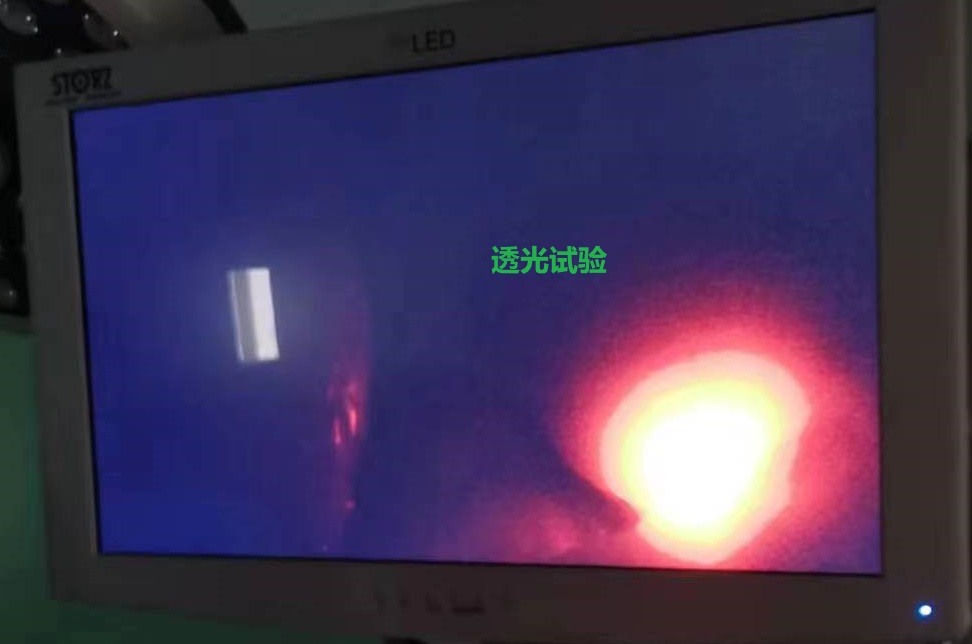

在征得小红及其家属同意后,5月25日,妇科团队为其在全麻下行腹腔镜联合宫腔镜探查,术中发现腹腔积血约100ml,盆腔内两个不相连的子宫,行腹腔镜下透光试验,确认左侧子宫为残角子宫,确认后再行腹腔镜下左侧残角子宫切除+左侧输卵管切除+左侧卵巢囊肿剔除术,手术非常顺利,术后在妇科团队的精心照料下,于5月31日痊愈出院。